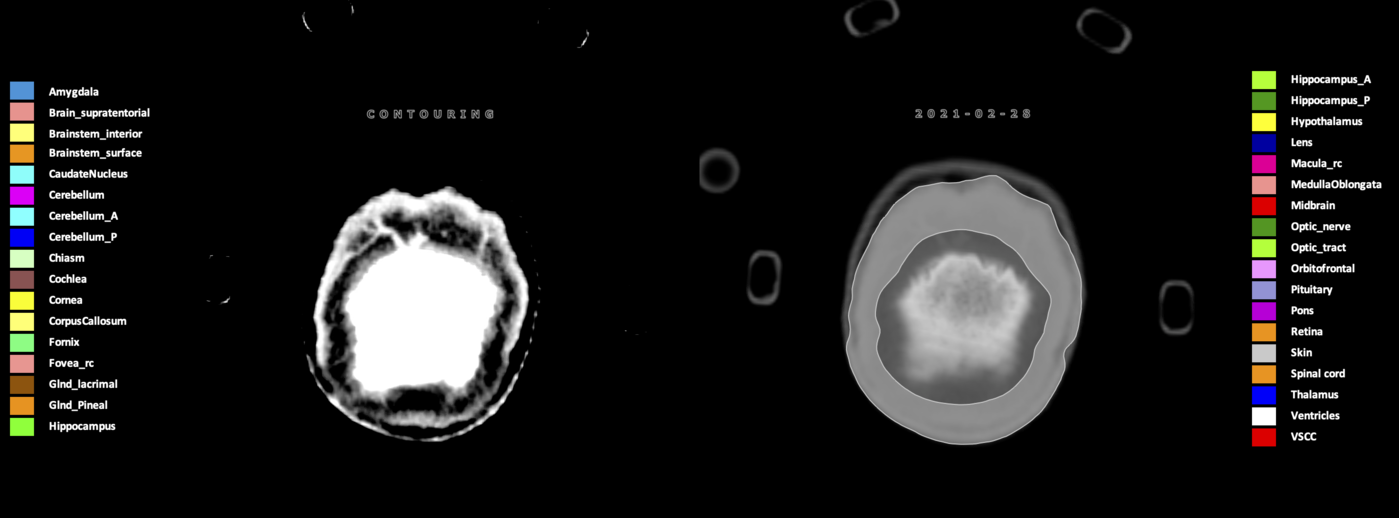

Eekers et al. have published an international neurological atlas for contouring of organs at risk in consensus with the European Particle Therapy Network (EPTN) in 2018 and an update in 2021. The purpose of this consensus atlas is to decrease inter- and intra-observer variability in delineating OARs relevant for neuro-oncology.

Included are all OARs known to be relevant for radiation-induced toxicity in neuro-oncology: brain, brainstem (midbrain, pons, medulla oblongata), chiasm, cerebellum (anterior & posterior), cochlea, cornea, hippocampus (anterior & posterior), hypothalamus, lens, lacrimal gland, optic nerve, pituitary, skin, and vestibular & semicircular canals. To further facilitate research on cognition, vision and radiological changes after irradiation of the brain, potential clinically-relevant OARs are included: amygdala, caudate nucleus, cerebellum (anterior & posterior), corpus callosum, fornix, macula, optic tract, orbitofrontal cortex, periventricular space (PVS), pineal gland, and thalamus.

Three-dimensional delineation of the 25 consensus OARs for neuro-oncology are shown on CT (WW/WL 120/40, 3000/600), 3T MR images, (T1Gd, T2FLAIR 1mm) and 7T MR (MP2RAGE 0.7 mm). All are presented in transversal, sagittal and coronal view.